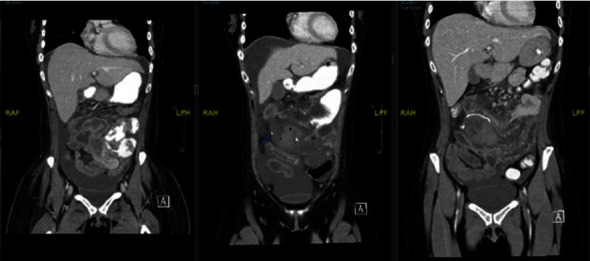

Although fungal infections causing intestinal perforation and necrosis are rare, they can be particularly dangerous in immunosuppressed patients, often leading to increased mortality rates and poor prognoses. Candida species are typically surface fungi, but in patients with compromised immune systems, they can invade the small intestine and cause angioinvasive infections. A case study involving a 30-year-old female with acute myeloid leukemia (AML) illustrates this phenomenon. The patient was presented with symptoms of abdominal pain, fever, diarrhea, recurrent episodes of intestinal necrosis, hematomas due to thrombocytopenia, and subsequent postoperative enterocutaneous fistulas. Extensive testing ruled out other possible causes of intestinal necrosis and enteritis, including Crohn's and CMV diseases. Candida guilliermondi was ultimately identified in blood cultures from the periphery, peritoneal fluid, and intestinal biopsy of respected sections, indicating that it was responsible for intestinal invasion and necrosis. The patient was then treated with amphotericin B, cefepime, and metronidazole. This case highlights the potential severity of fungal infections in immunosuppressed patients, particularly Candida species, and the importance of prompt diagnosis and appropriate treatment.